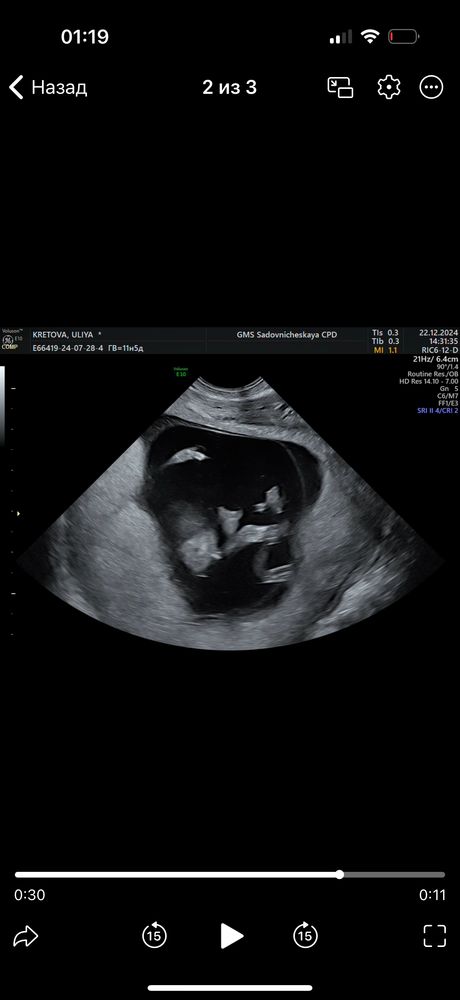

С первого скринга жаркие споры по поводу пола нашего малыша 😁 Сегодня 15 недель 5 дней, но по размеру плода мне ставят 15 и 2. На ранних сроках чуть позже увидели эмбрион (я еще испугалась, что его нет в пя), в итоге сказали, что вероятнее всего, была поздняя овуляция.

сегодгя было сложно что-то рассмотреть, с нетерпением жду 2 скрининга, но мне очень уж интересно, какого пола наше сокровище. Посмотрите на фотку и сделайте свои предположения, пожалуйста ☺️ Как я понимаю, это вид спереди😁

Eva , вот я попробовала скрин сделать, там как будто в определенный момент между ножек беленькая палочка была, я думала, что это м. А вот на сегодняшней фотке не совсем гладко, но и нет выраженной ясности)

Юлия Флинк, к сожалению на фотках с 1 скрининга не разберешь, а вот если на фотках вашего последнего узи вид между ножек( скорее всего да), то похоже на мальчика

Юлия Флинк, тогда это скорее всего пацан, если торчит между ног. у меня аналогично также было на узи 14,5(можете у меня в дневнике посмотреть). узистка заверила меня, что это уже 100% . но некоторые на бб я видела писали, что пол окончательно формируется после 15-16 недель. так что будем ждать 2 скрининг)